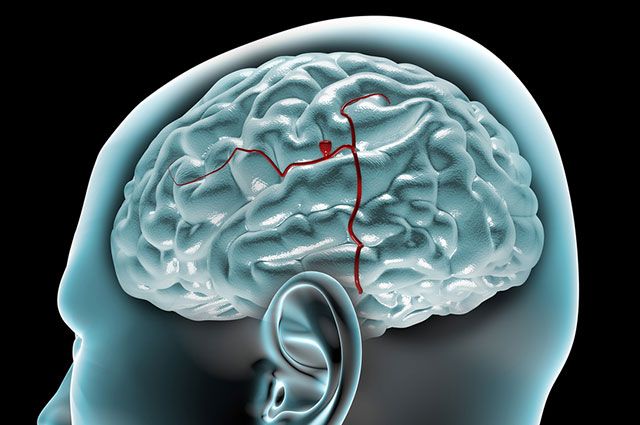

Снимки и иллюстрации микроаневризм сосудов головного мозга

:format(webp):quality(80)/https%3A%2F%2Fwww.csid.ro%2Fwp-content%2Fuploads%2F2020%2F05%2F17889730%2F1-anevrism-cerebral.jpg)